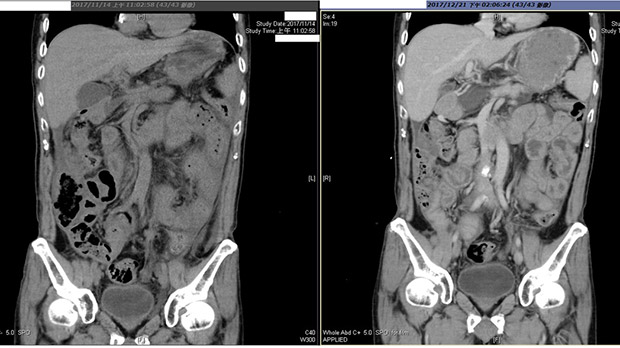

(胰臟癌轉移腹膜患者林先生住院治療大半年,去年11月腸子已被癌細胞侵吞阻塞〔左圖〕,無法進食、疼痛不堪,施打治感冒的化痰藥1個月後〔右圖〕,竟能開始進食,腫瘤也消褪,出院後仍持續回診施打。圖/黃冠誠醫師提供)